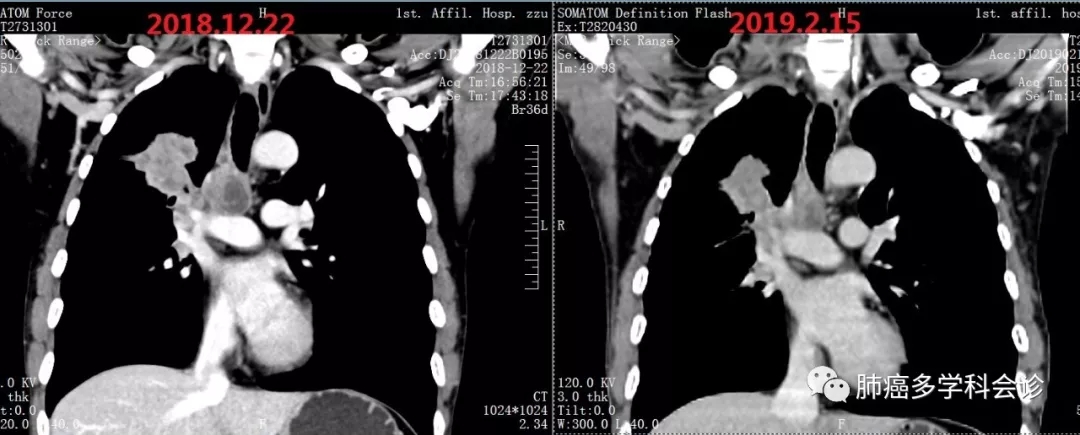

于2018-9-10 开始“培美曲塞+顺铂”化疗,共 4周期,肿瘤没有明显变化,评价疗效:SD。化疗致严重消化道反应,曾呕吐出咖啡色液体(可能系口服非甾体类止痛药及严重呕吐引起胃出血),体重下降5kg。2018-12复查CT提示疾病进展。PS 2-3 分

患者参加研究者发起的临床试验,于2018.12.27开始静脉滴注国产PD-1抗体(SHR1210),每次200mg。自诉第一周期治疗后食欲增加、下床活动明显增多。经 2周期治疗后,复查CT显示病灶较前减小:

3.webp.jpg11.webp.jpg治疗4个周期后复查,原发灶较前有所增大: